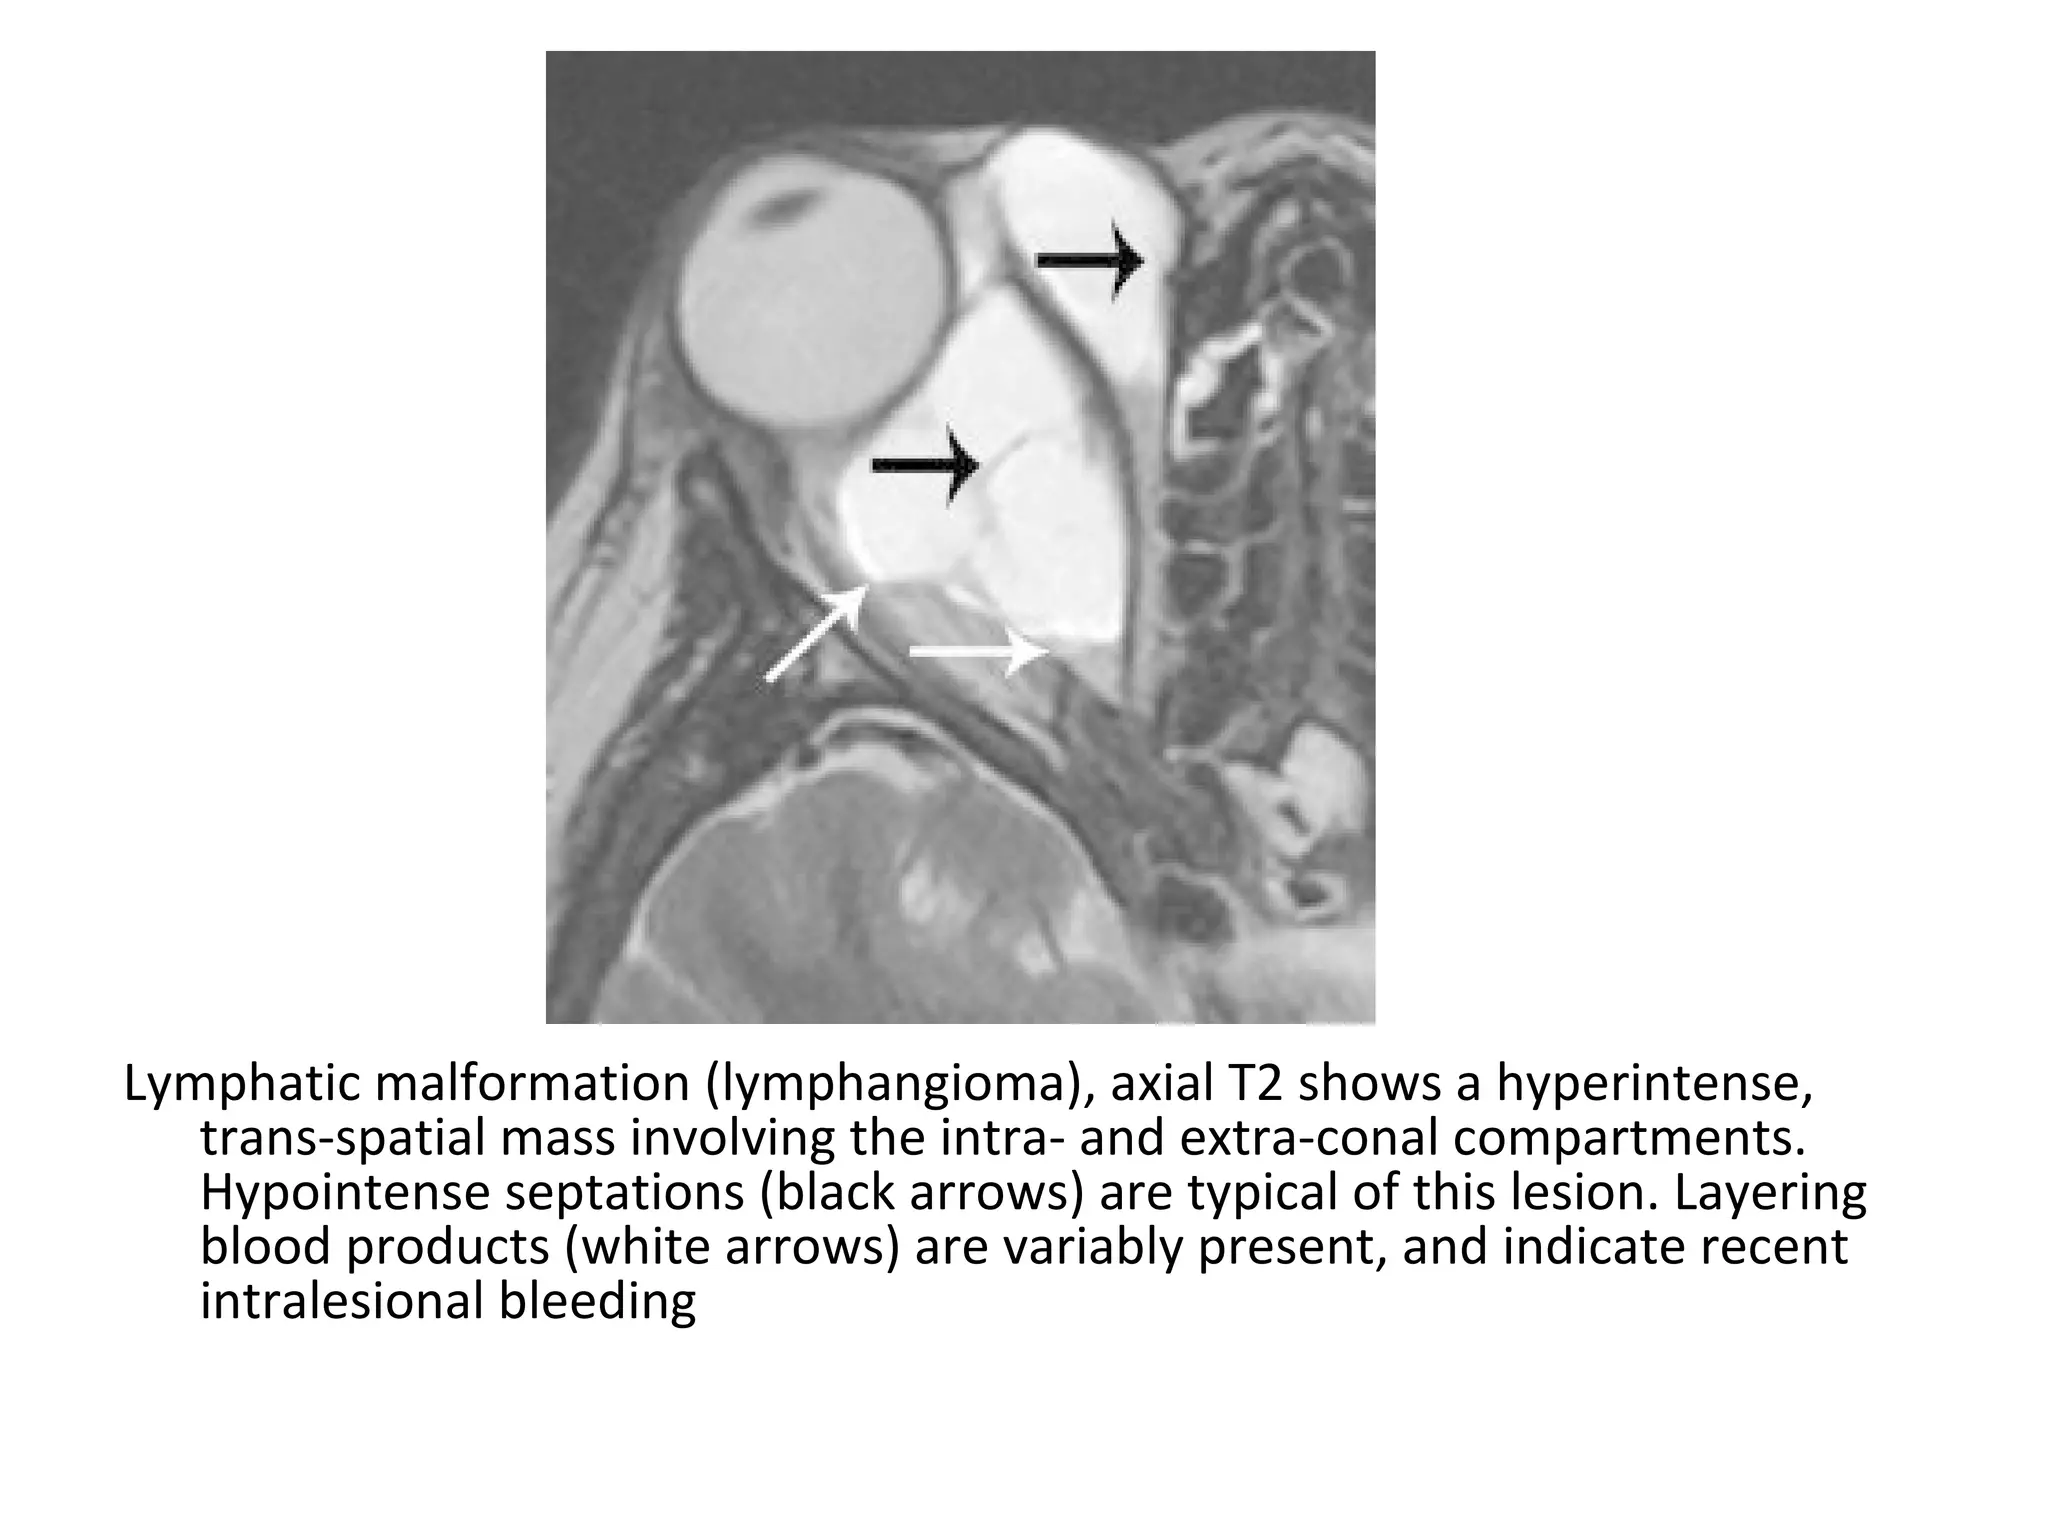

Lymphatic malformation (lymphangioma), axial T2 shows a hyperintense,

trans-spatial mass involving the intra- and extra-conal compartments.

Hypointense septations (black arrows) are typical of this lesion. Layering

blood products (white arrows) are variably present, and indicate recent

intralesional bleeding